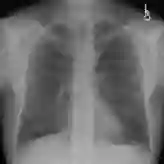

Despite the progress in utilizing deep learning to automate chest radiograph interpretation and disease diagnosis tasks, change between sequential Chest X-rays (CXRs) has received limited attention. Monitoring the progression of pathologies that are visualized through chest imaging poses several challenges in anatomical motion estimation and image registration, i.e., spatially aligning the two images and modeling temporal dynamics in change detection. In this work, we propose CheXRelNet, a neural model that can track longitudinal pathology change relations between two CXRs. CheXRelNet incorporates local and global visual features, utilizes inter-image and intra-image anatomical information, and learns dependencies between anatomical region attributes, to accurately predict disease change for a pair of CXRs. Experimental results on the Chest ImaGenome dataset show increased downstream performance compared to baselines. Code is available at https://github.com/PLAN-Lab/ChexRelNet